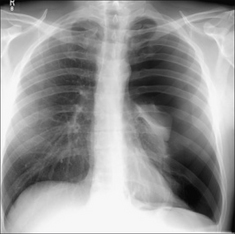

image

Figure 28.2 Acute dyspnoea. Lungs clear. Both domes of the diaphragm are high. Apply Golden Rule 1—clinical details are crucial. Abdomen is distended with a succussion splash when shaken. CXR conclusion—ascites displacing the diaphragm upwards.